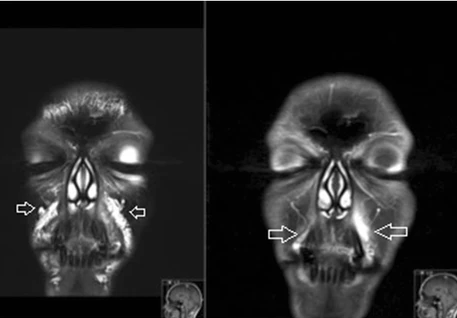

Periorbital “bags” primarily reflect herniation/ptosis of orbital fat and variable fluid retention beneath progressively thinner eyelid skin. Despite pervasive marketing, topical products cannot remove adipose tissue.

Hyaluronic acid fillers can stay in the body for 12 years or longer and migrate.